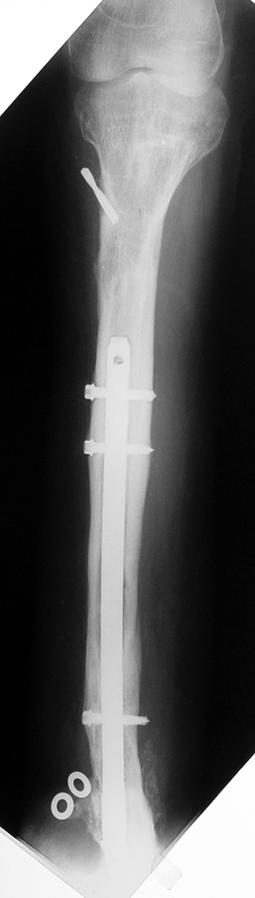

3- POSTTRAVMATİK BACAK KISALIĞI (YANLIŞ KAYNAMA)

Bu Bacak Kısalık tipi bir kırığın kısalmış pozisyonda kaynaması ile oluşur. Bir çok vaka yetişkinlerde görülür ve sadece bir uzatma ile tedavi edilebilir. Ek deformiteler de aynı anda düzeltilebilir. Bu hastaların çoğu çivi üzerinden uzatma veya tam implante edilen çivi ile tedavi edilebilirler.